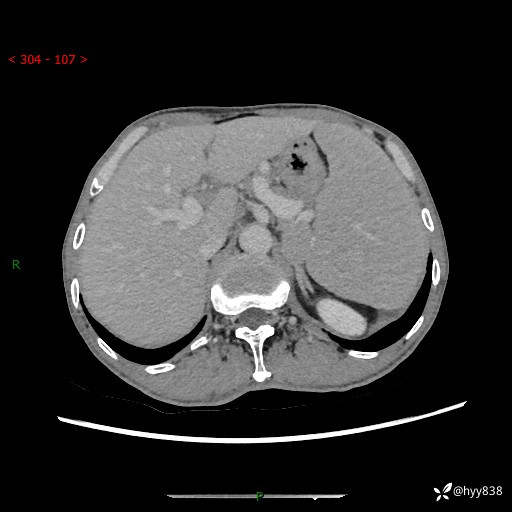

老年男性,脾大并脾脏弥漫粟粒状低密度,淋巴瘤 VS 肉芽肿 VS 血管瘤---结果公布

简要病史: 患者于3月前无明显诱因出现脾大,伴腹部轻微不适,具体不详,无腹痛、腹泻、腹胀,无头晕、头痛、乏力,无恶心、呕吐、呕血,无胸闷、气短、胸痛不适

上腹部CT平扫+增强